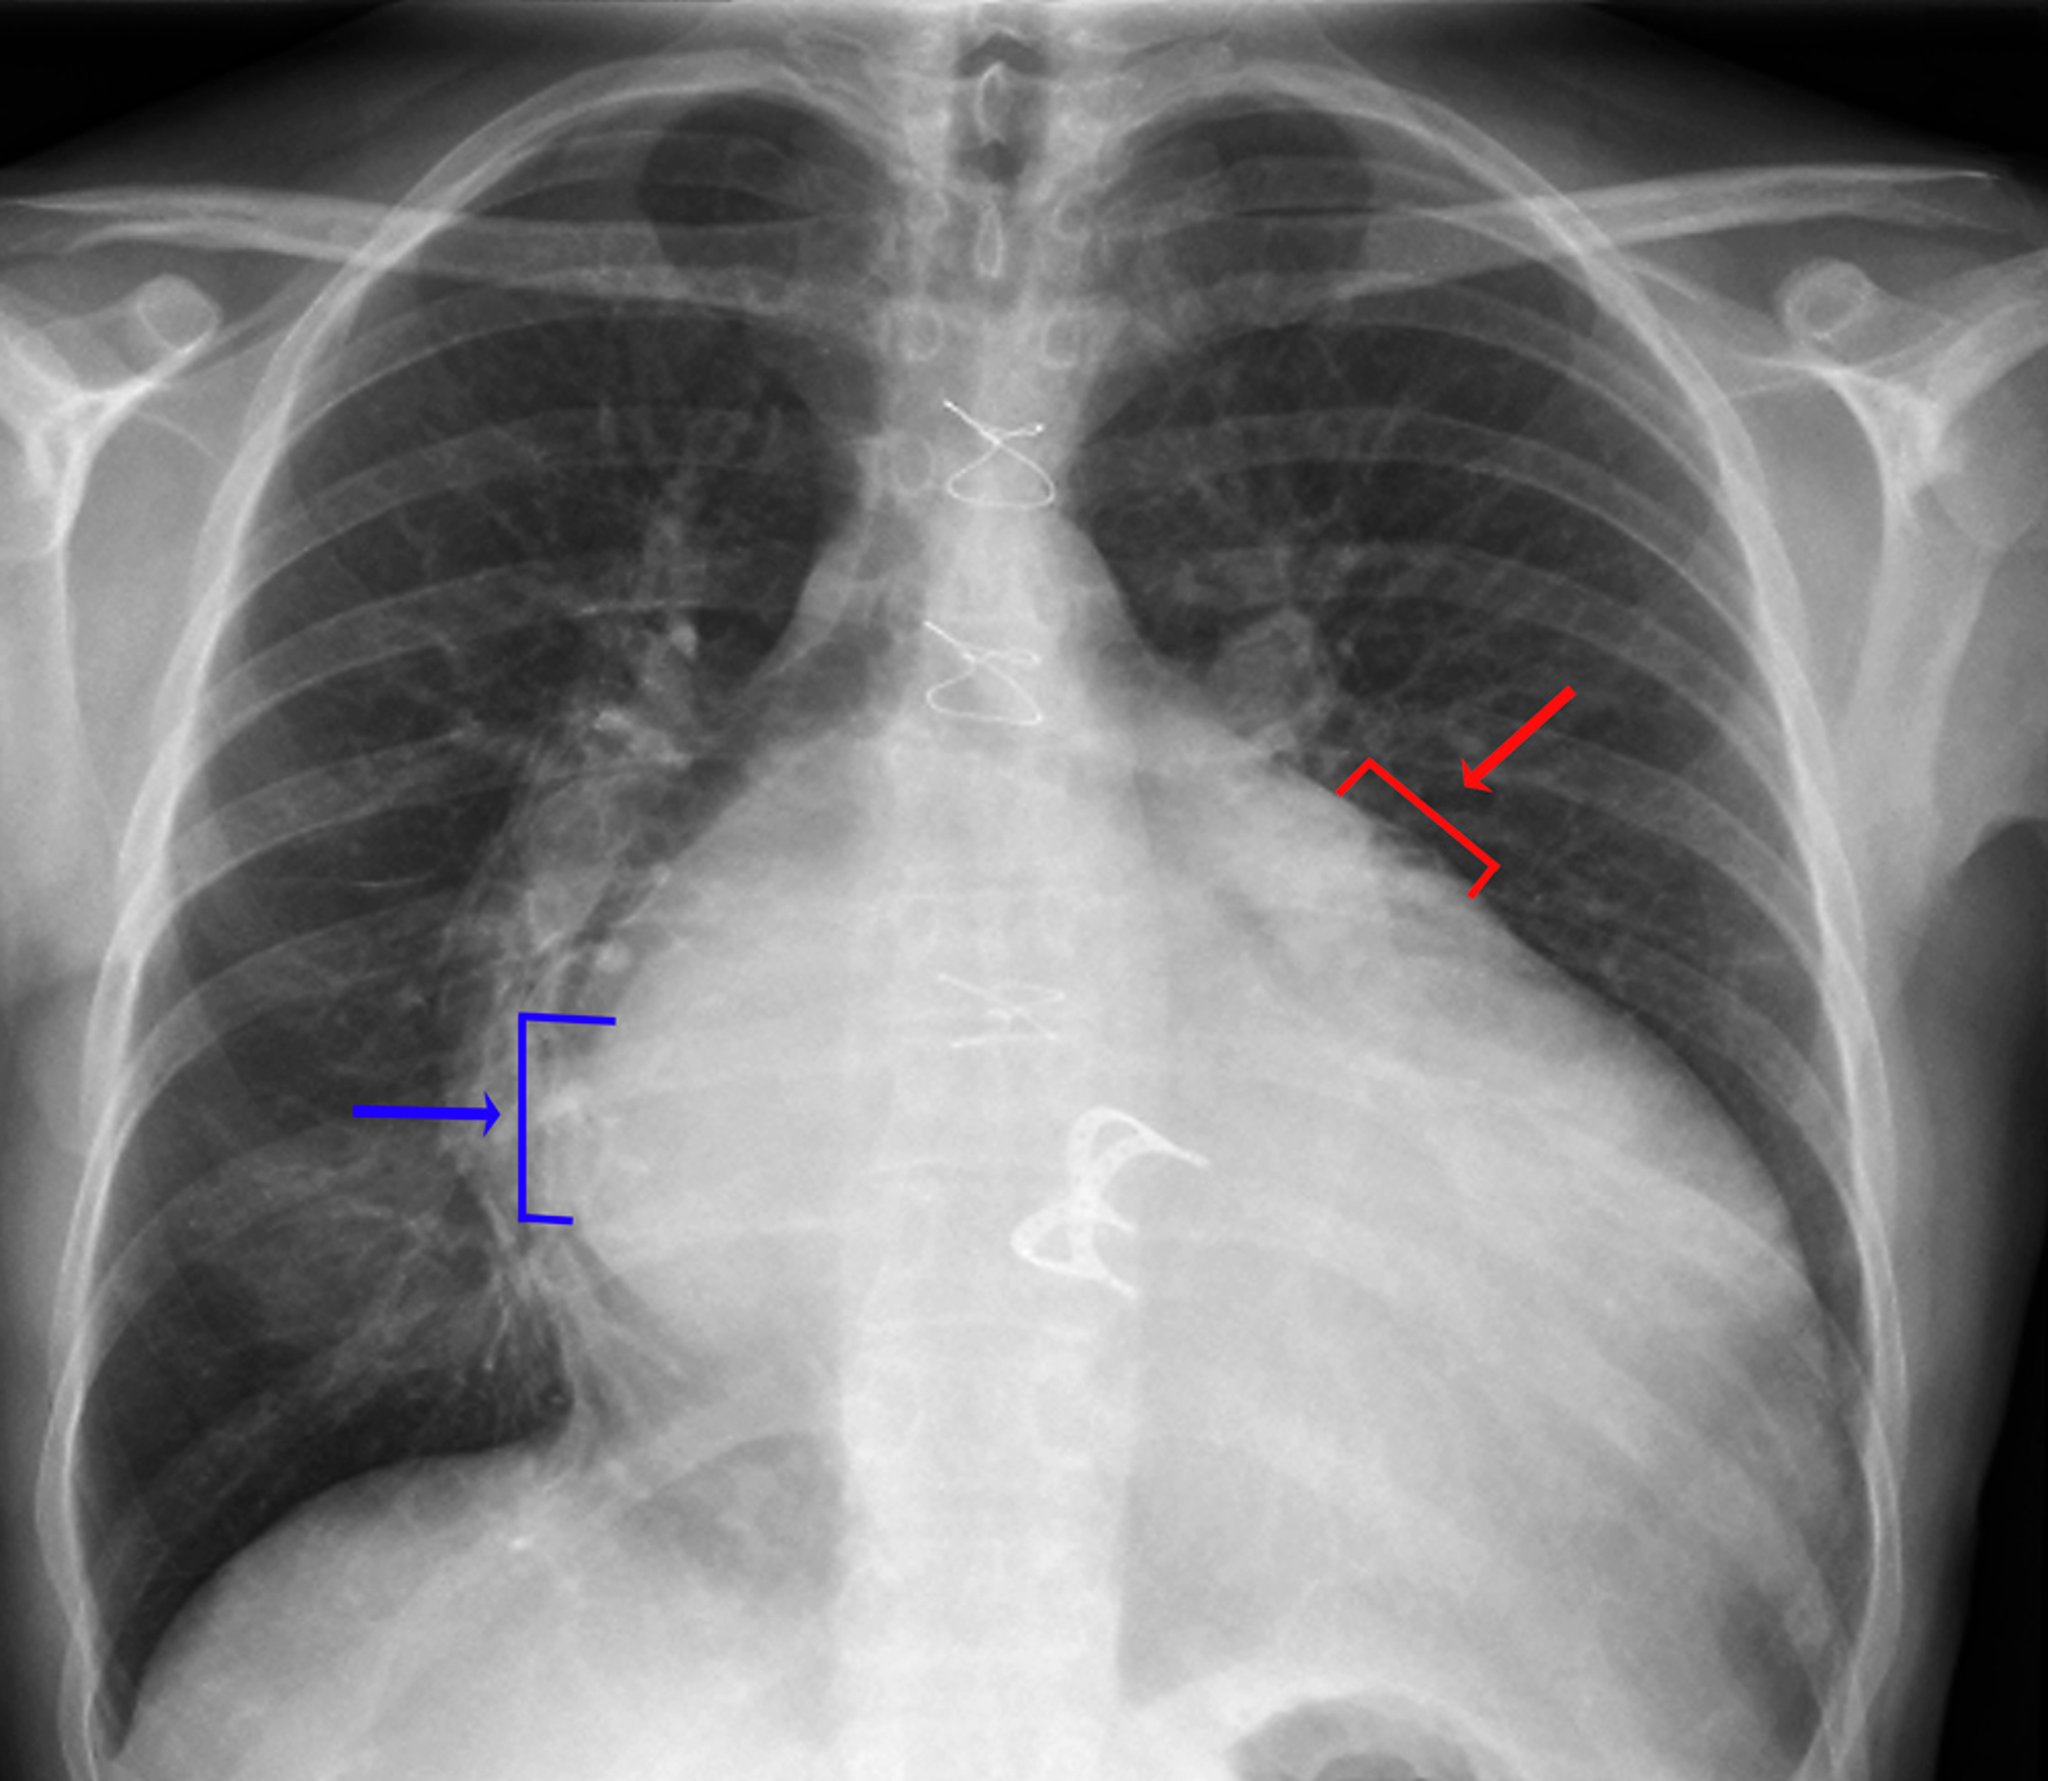

Radiografia de tórax (prótese de valva cardíaca)

Sinais de aumento do átrio esquerdo incluem densidade visível do átrio esquerdo no hemitórax direito (seta azul, sinal de dupla densidade), maior distância (> 7 cm) entre a borda atrial esquerda no hemitórax direito e o brônquio principal esquerdo, convexidade ao longo da borda superior esquerda do coração causada pelo aumento do apêndice atrial esquerdo (seta vermelha) e alargamento da carina com maior separação entre os brônquios principais esquerdo e direito. Sinais de aumento do ventrículo esquerdo incluem aumento evidente da silhueta cardíaca e deslocamento da borda cardíaca esquerda para baixo e para a esquerda.